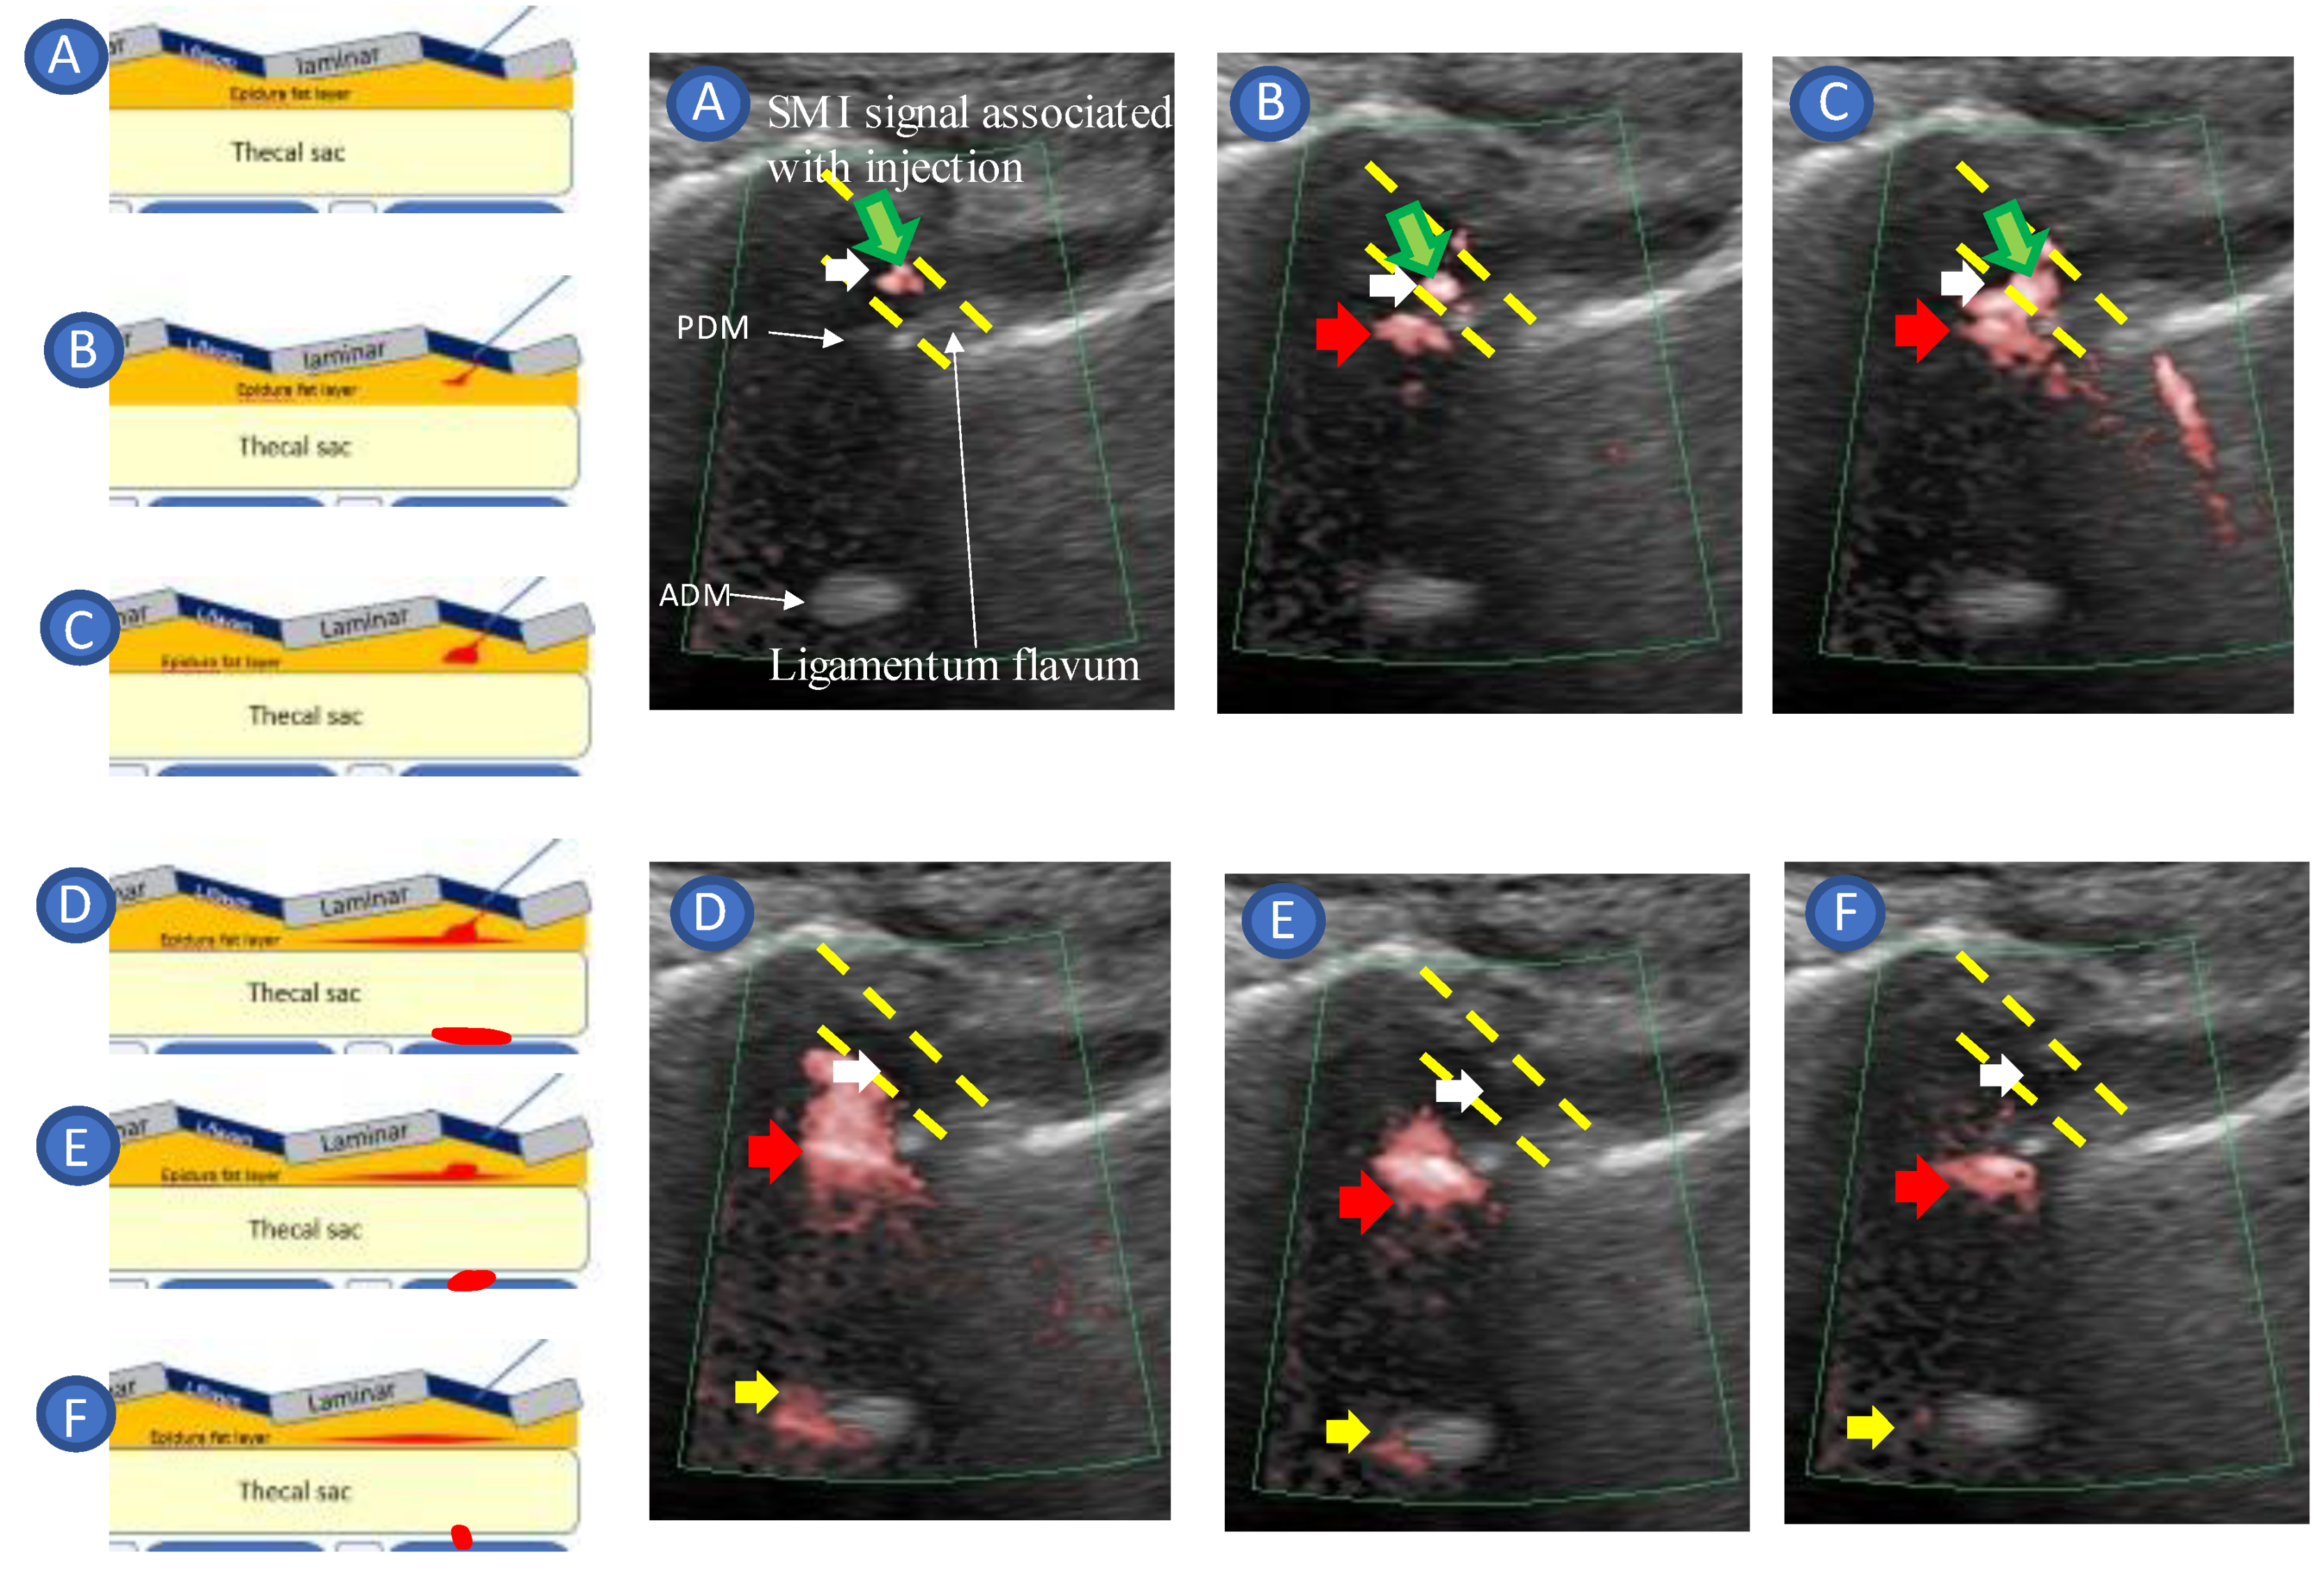

- Accurate needle tip guidance into the ligamentum flavum behind the epidural fat layer;

- Palpation of resistance by finger sense during ligamentum flavum insertion while confirming with sonography;

- Confirmation of the position of the needle tip in the ligamentum flavum;

- Tracing the spread of the drug in the epidural space using SMI during the injection.